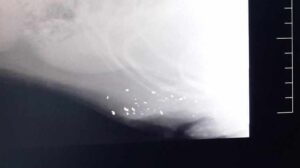

Auf dem Röntgenbild sieht man die ganzen Kugeln. Ich werde nie begreifen, was in den Köpfen von solch empathielosen und brutalen A…. vor sich geht!

Die letzten beiden Wochen habe ich euch ja von Nadija und ihrer fortschreitenden Genesung erzählt. Inzwischen musste der nächste Fundhund direkt operiert werden. Diesmal allerdings einer, den jemand zu Schießübungen mit der Schrotflinte benutzt hat. Davon abgesehen hat Hero, so hat Karin ihn getauft, auch ein gebrochenes Vorderbein.

Hier sieht man ihn direkt nach seiner Einlieferung in der Klinik. Ich möchte mir nicht ausmalen, wie es ihm ergangen wäre, wenn wir nicht sofort kontaktiert worden wären.

Momentan müssen wir erstmal etwas abwarten, ob oder inwieweit auch ein Nerv verletzt wurde, bzw. bis und wie Hero sein Beinchen wieder belastet. Je nachdem werden wir dann die bestmöglich Lösung für sein Bein finden. Was wir uns aber jetzt schon wünschen ist zunächst eine Pflegestelle (gerne natürlich auch mit Übernahme oder einem festen Platz) für ihn in Deutschland, da es hier einfach umfangreichere medizinische Möglichkeiten der Nachbehandlungen gibt, so die nötig werden sollten. Bis er reisen kann wird es natürlich noch eine ganze Weile dauern, aber da wir noch nicht wissen was da auf seine Pflegestelle zu kommt, denke ich es ist klug möglichst früh mit der Suche zu beginnen. Ansonsten drückt ihm herzlich gerne alle die Daumen.